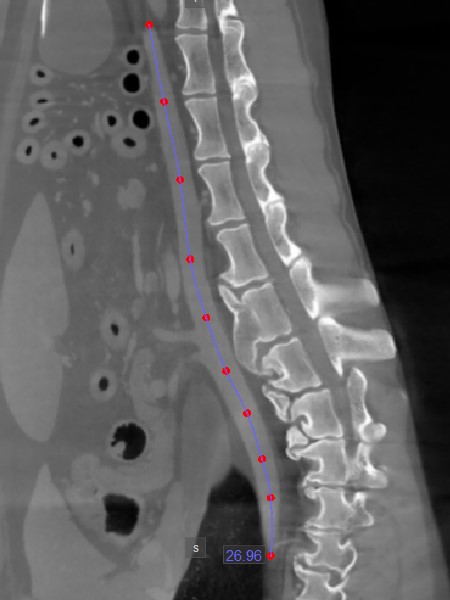

Path Length¶

The Path Length

tool offers users the ability to measure the length of irregular lines or the outline of intricate shapes along a non-linear path.

Select the Path Length

and assign it to one of the available mouse buttons. Start the measurement by placing points along a non-linear path on the active image slice. As the user places the points, the software

automatically connects and creates the path.

Complete the measurement by double-clicking when placing the last point of the path, or use the right mouse button to immediately calculate the path. The length of the path is displayed alongside the measurement.

Modify the path by moving one of the points describing it using the Default

tool.